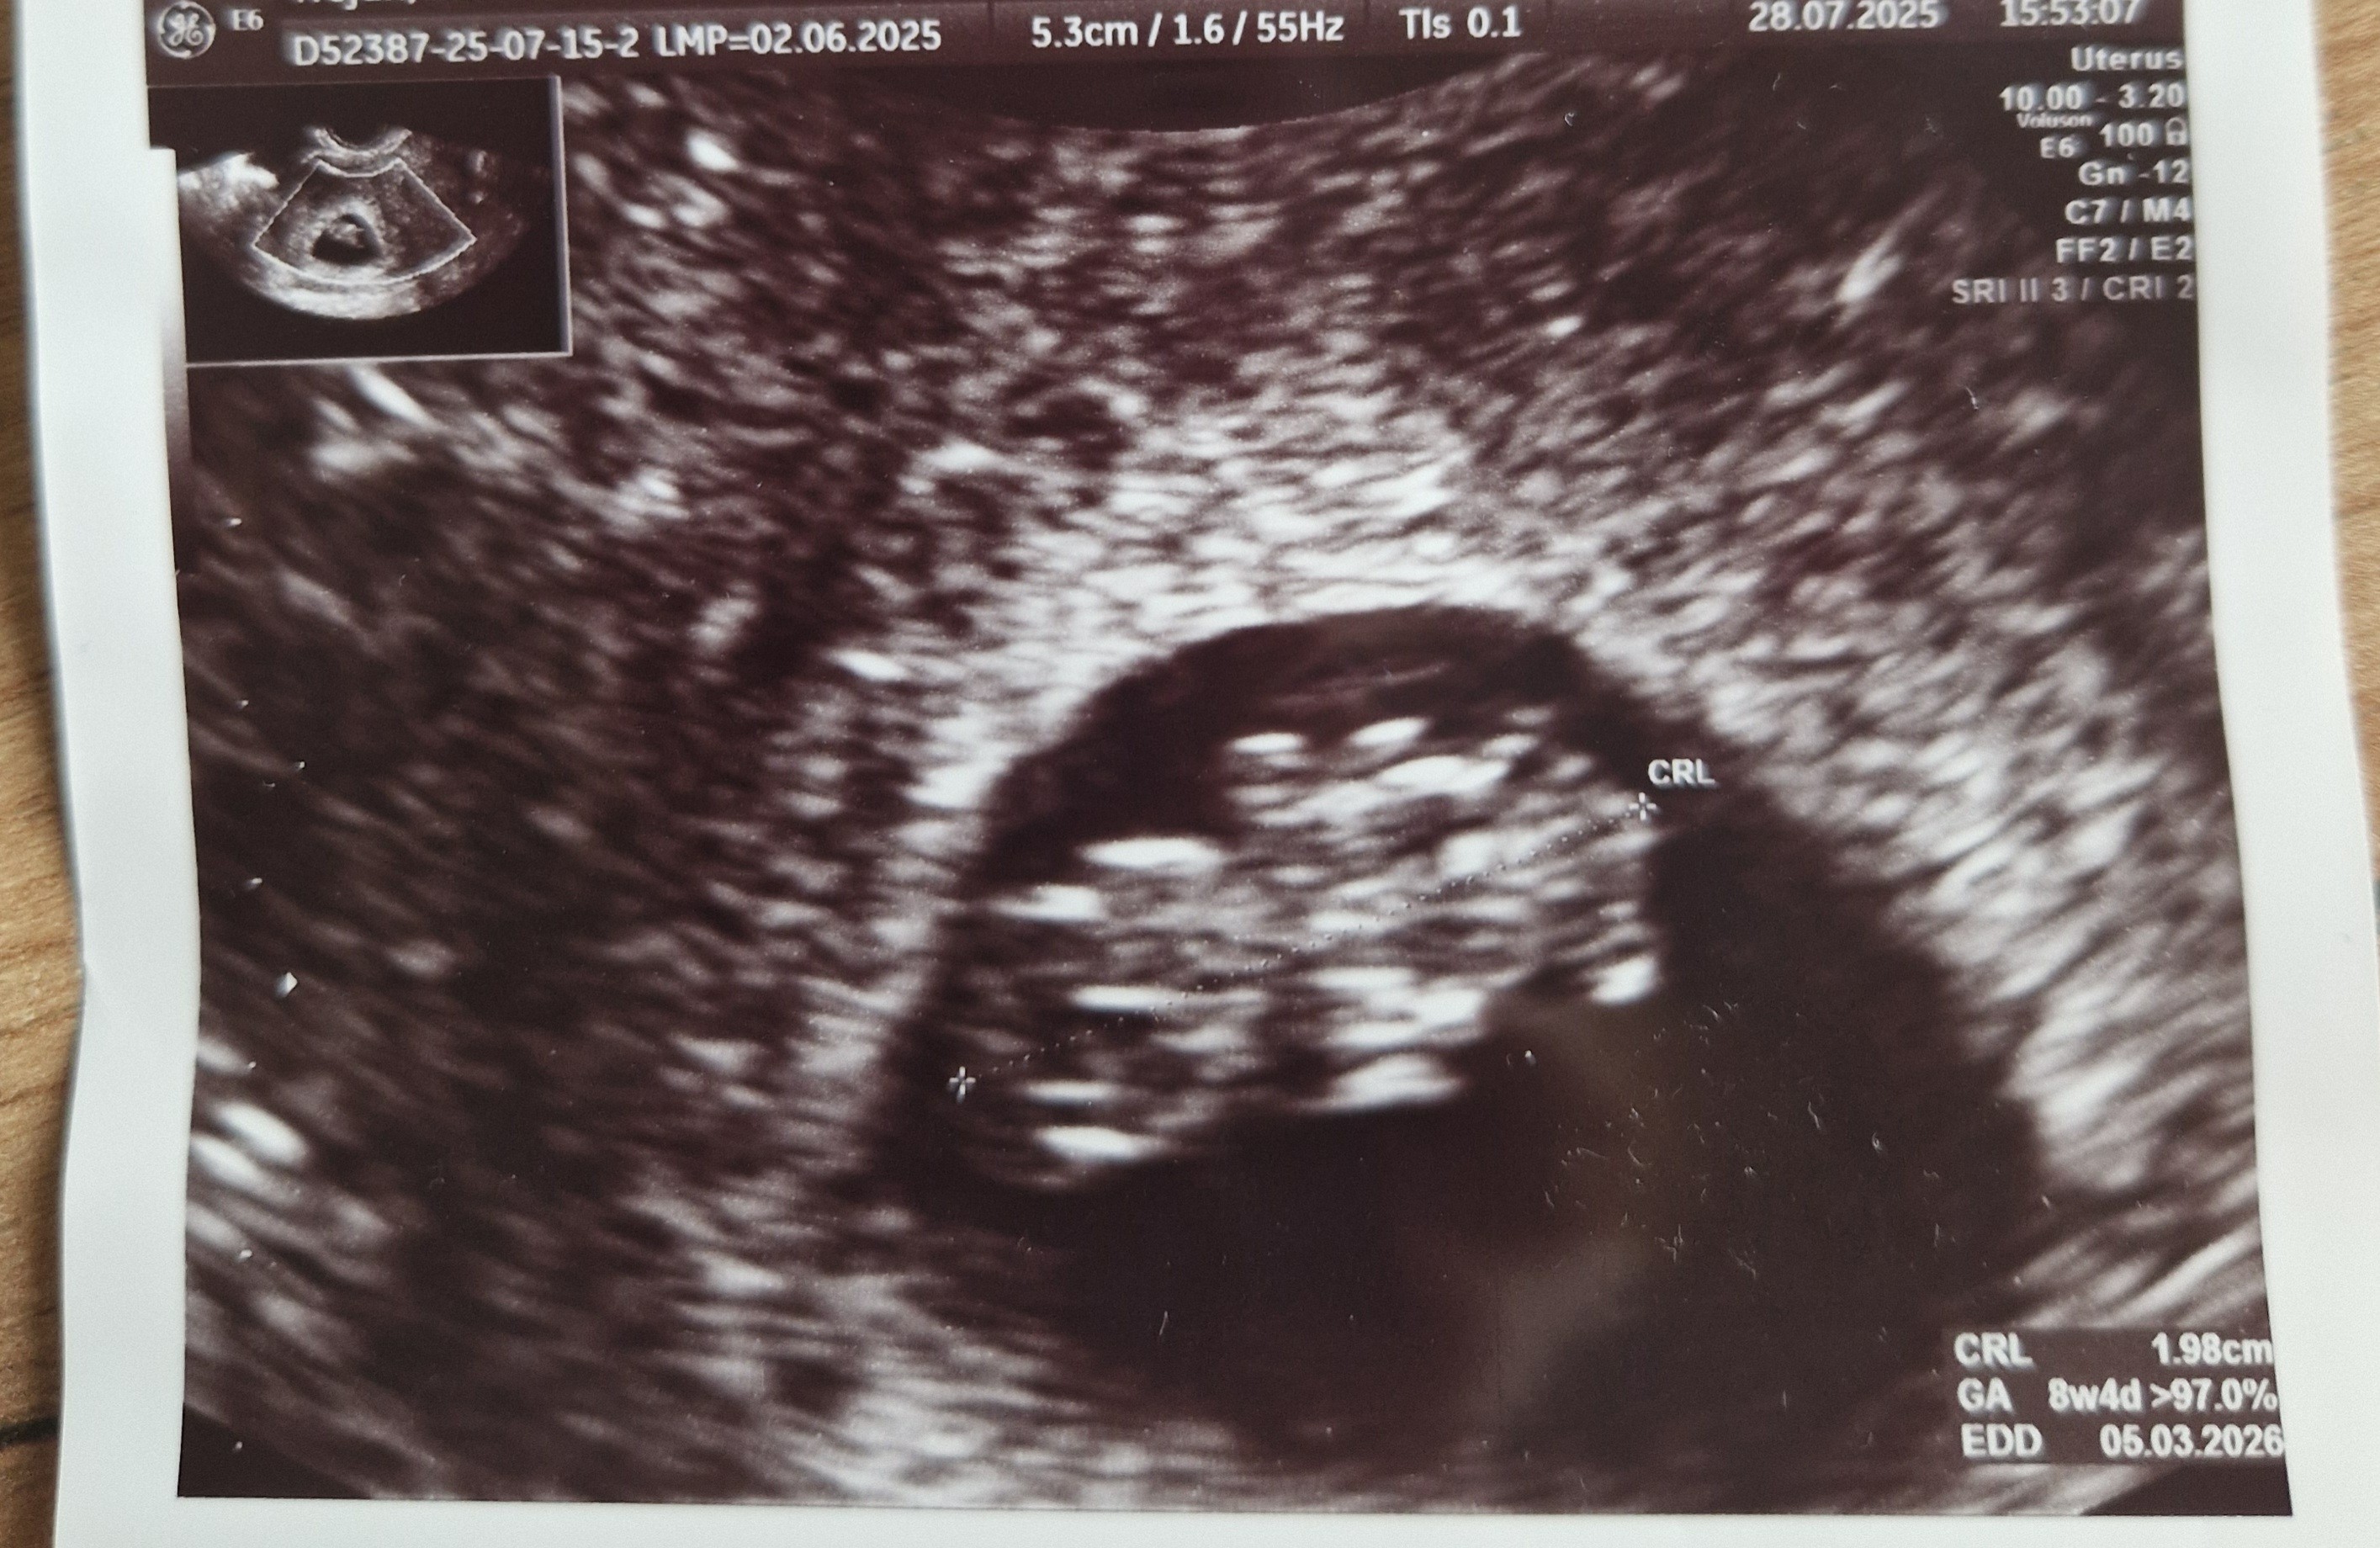

Hej dziewczyny, to i ja się zamelduje z kontrolnej wizyty w tym tygodniu😊 Fasolka przyspieszyła nieco i termin z USG wychodzi na 05.03, ostatnio było 08.03. Jest delikatna rozbieżność co do terminu z OM, ale niewielka i tak się ponoć często zdarza. Póki co jest wszystko w porządku, na razie mam się nie martwić rozjechanymi wynikami morfologii. Czuję się w miarę ok pomijajac mega ssanie w żołądku i mdłości jak nie zjem o czasie. Jak uważacie do którego tygodnia jest czas na zmianę lekarza? Obecnie 9+1

• 20250731_103950.jpg

20250731_103950.jpg

1 005,2 KB · Wyświetleń: 49